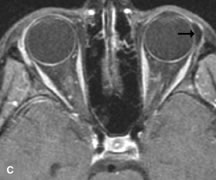

Fig. 18. A. T1-weighted, (B) T2-weighted fat-suppressed, and (C) T1-weighted fat-suppressed MR scans demonstrate a small dermoid cyst arising near the palpebral portion of the lacrinal gland (arrows). The lesion is similar in signal intensity to fat on the T1-weighted scan (A) consistent with a high adipose tissue content. The lesion shows fat-suppression and low signal intensity on the two fat-suppressed sequences (B and C) confirming its high lipid content.

Dermoid cysts appear as rounded, well-defined lesions typically contiguous with an orbital bony suture. The high-intensity signal on T1-weighted images is attributed to the sebaceous-produced lipid contents (Fig. 18).31,50 Mucoceles may demonstrate a hypointense or hyperintense signal on MR images, depending on the concentration of proteinaceous or inflammatory fluid components. The integrity of the bony walls of the expanded sinus cavities cannot be assessed on MR as well as by CT.37,50,55,56 A high-signal intensity on Tl- and T2-weighted images is characteristic of orbital chronic hematic cysts because of the blood-breakdown products within the cysts.57